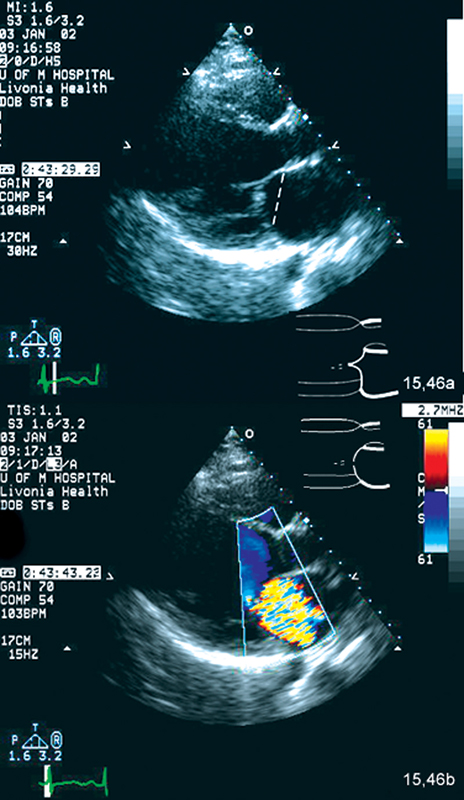

فحوصات تشخيصية لبعض امراض القلب والشرايين التاجية